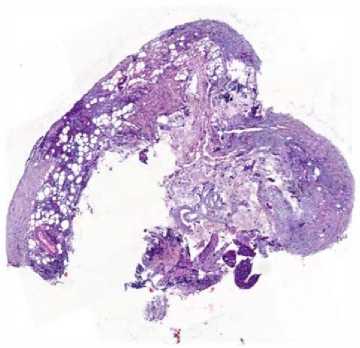

Рис. 4. Гистологические сканы перитонеальных метастазов до начала лечения (окрашивание гематоксилином и эозином, ув. ×50)

• Fig. 4.    Pre-treatment histopathological scans of peritoneal metastases (hematoxylin and eosin staining, ×50 magnification)

Рис. 7. Гистологические сканы перитонеальных метастазов после 6 курсов лечения (окрашивание гематоксилином и эозином, ув. ×50)

• Fig. 7.    Histopathological scans of peritoneal metastases after 6 treatment cycles (hematoxylin and eosin staining, ×50 magnification)